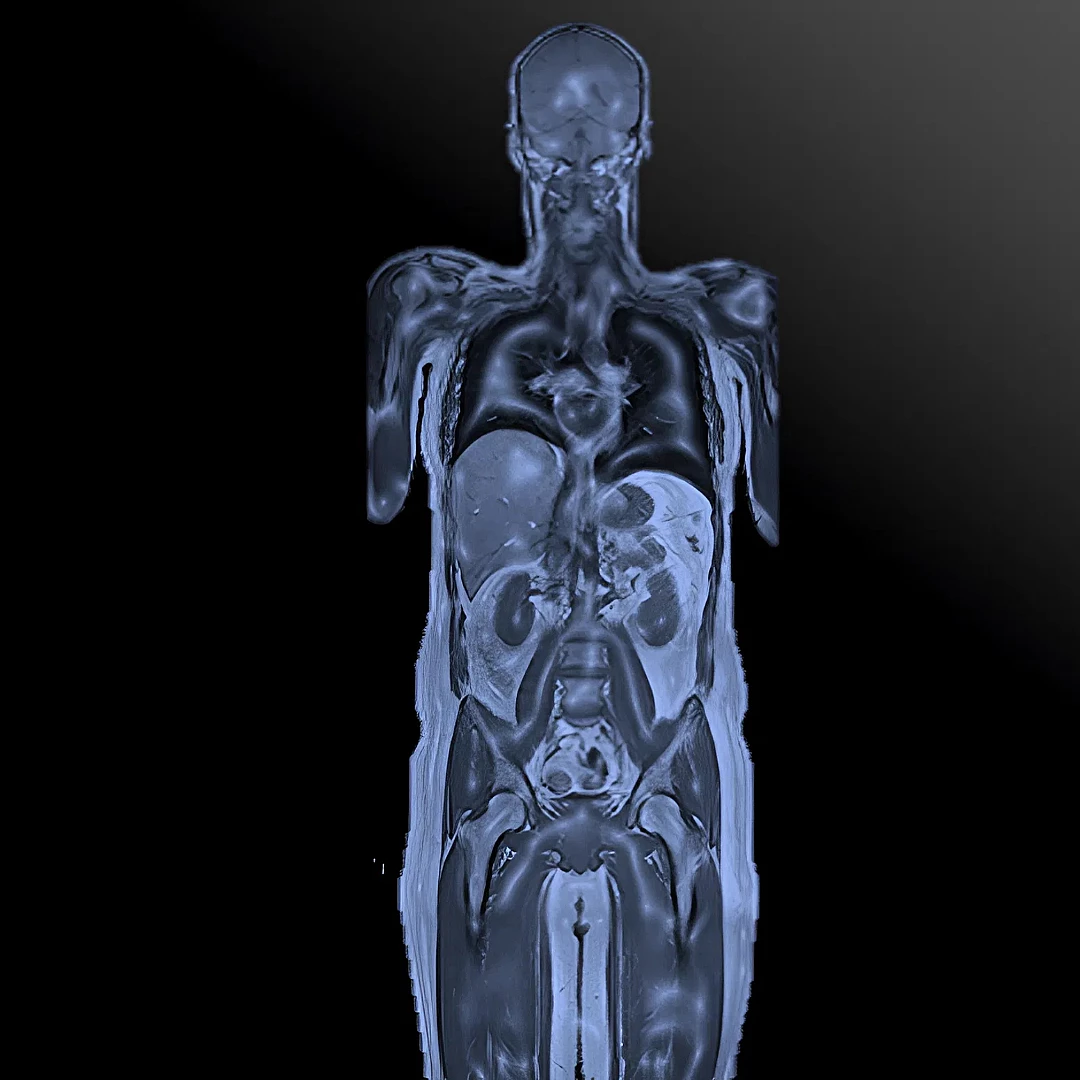

Whole Body MRI

Whole Body MRI is a comprehensive, radiation-free scan that captures detailed images of your entire body in one session. It’s ideal for early detection, preventive screening, and monitoring of systemic conditions.